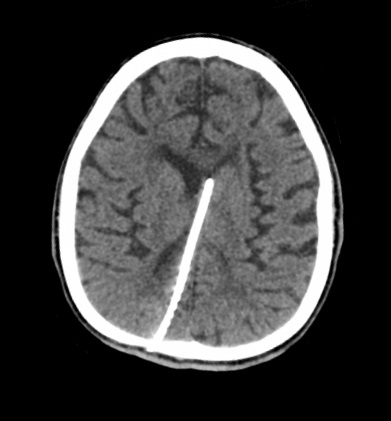

Objective: Normal embryonic and fetal development is strictly bound to maternal health and functioning placenta. Besides the invasion and differentiation of trophoblastic cell lineage; development of effective vasculature is crucial for the function of placenta. Placental vessels first arise by vasculogenesis in early development of villi and then succeeded by angiogenesis during fetal life. In the recent decades a new form of angiogenesis, “intussusceptive angiogenesis”, besides classical sprouting angiogenesis is well documented. The presence of intussusception was shown at multiple organs but in placenta, in recent literature. We aimed to determine whether intussusceptive angiogenesis is present in human placenta to obtain further evidence on the development of vascular bed. Methods: The term placenta samples were obtained from 10 healthy pregnancies following caesarean sections. Tissues were processed using routine plastic embedding technique; thin sections were contrasted with uranyl acetate & lead citrate; observed and photographed by transmission electron microscope. Results: Our examinations revealed that both sprouting and intussusceptive angiogenesis is present in floating villi of term placenta. Phases of intussusception were documented in various samples. Conclusion: The presence of intussusceptive angiogenesis will help our understanding of microvascular bed remodeling during pregnancy. We believe that this new finding will help us to determine the relation of microvascular bed development in normal and abnormal placentas.